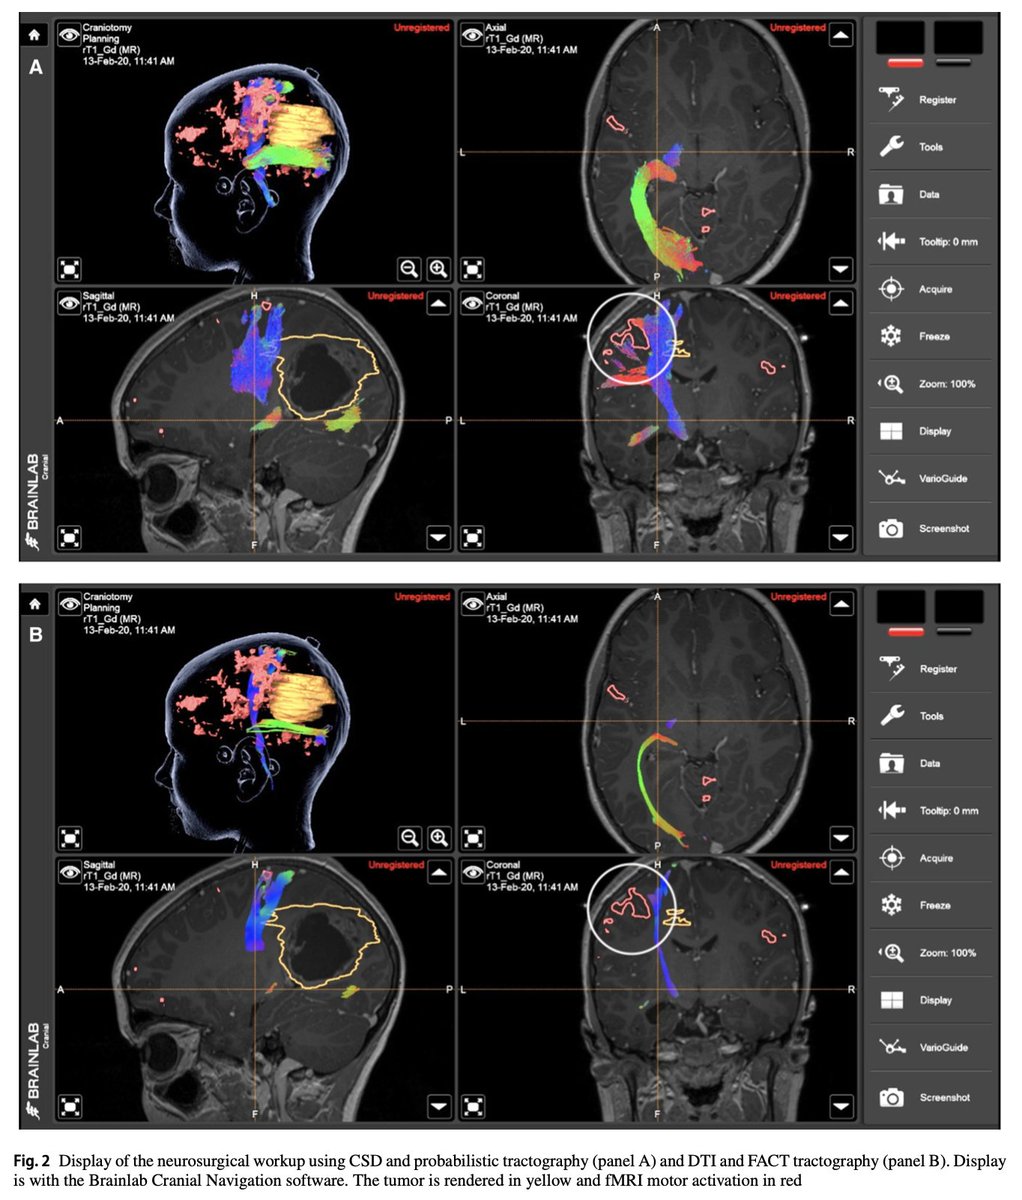

Our new paper on "Karawun", a software that converts track files (.tck) to DICOM. This allows advanced tractography to be leveraged for presurgical planning and be displayed and used during neurosurgery. link.springer.com/article/10.100…